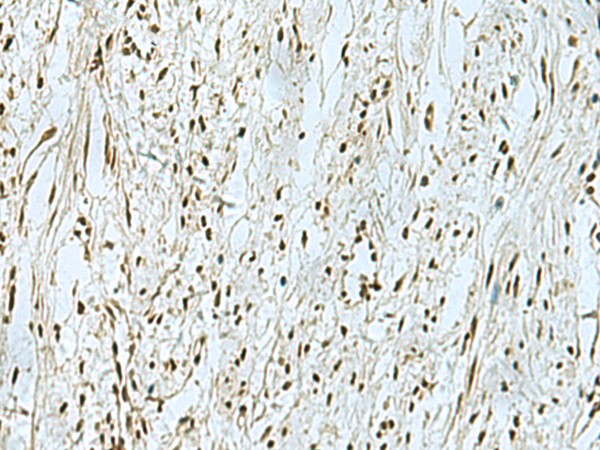

IHC (Immunohiostchemistry)

(The image is immunohistochemistry of paraffin-embedded Human breast cancer tissue using 47370(THTPA Antibody) at dilution 1/90.(Original magnification: 200))